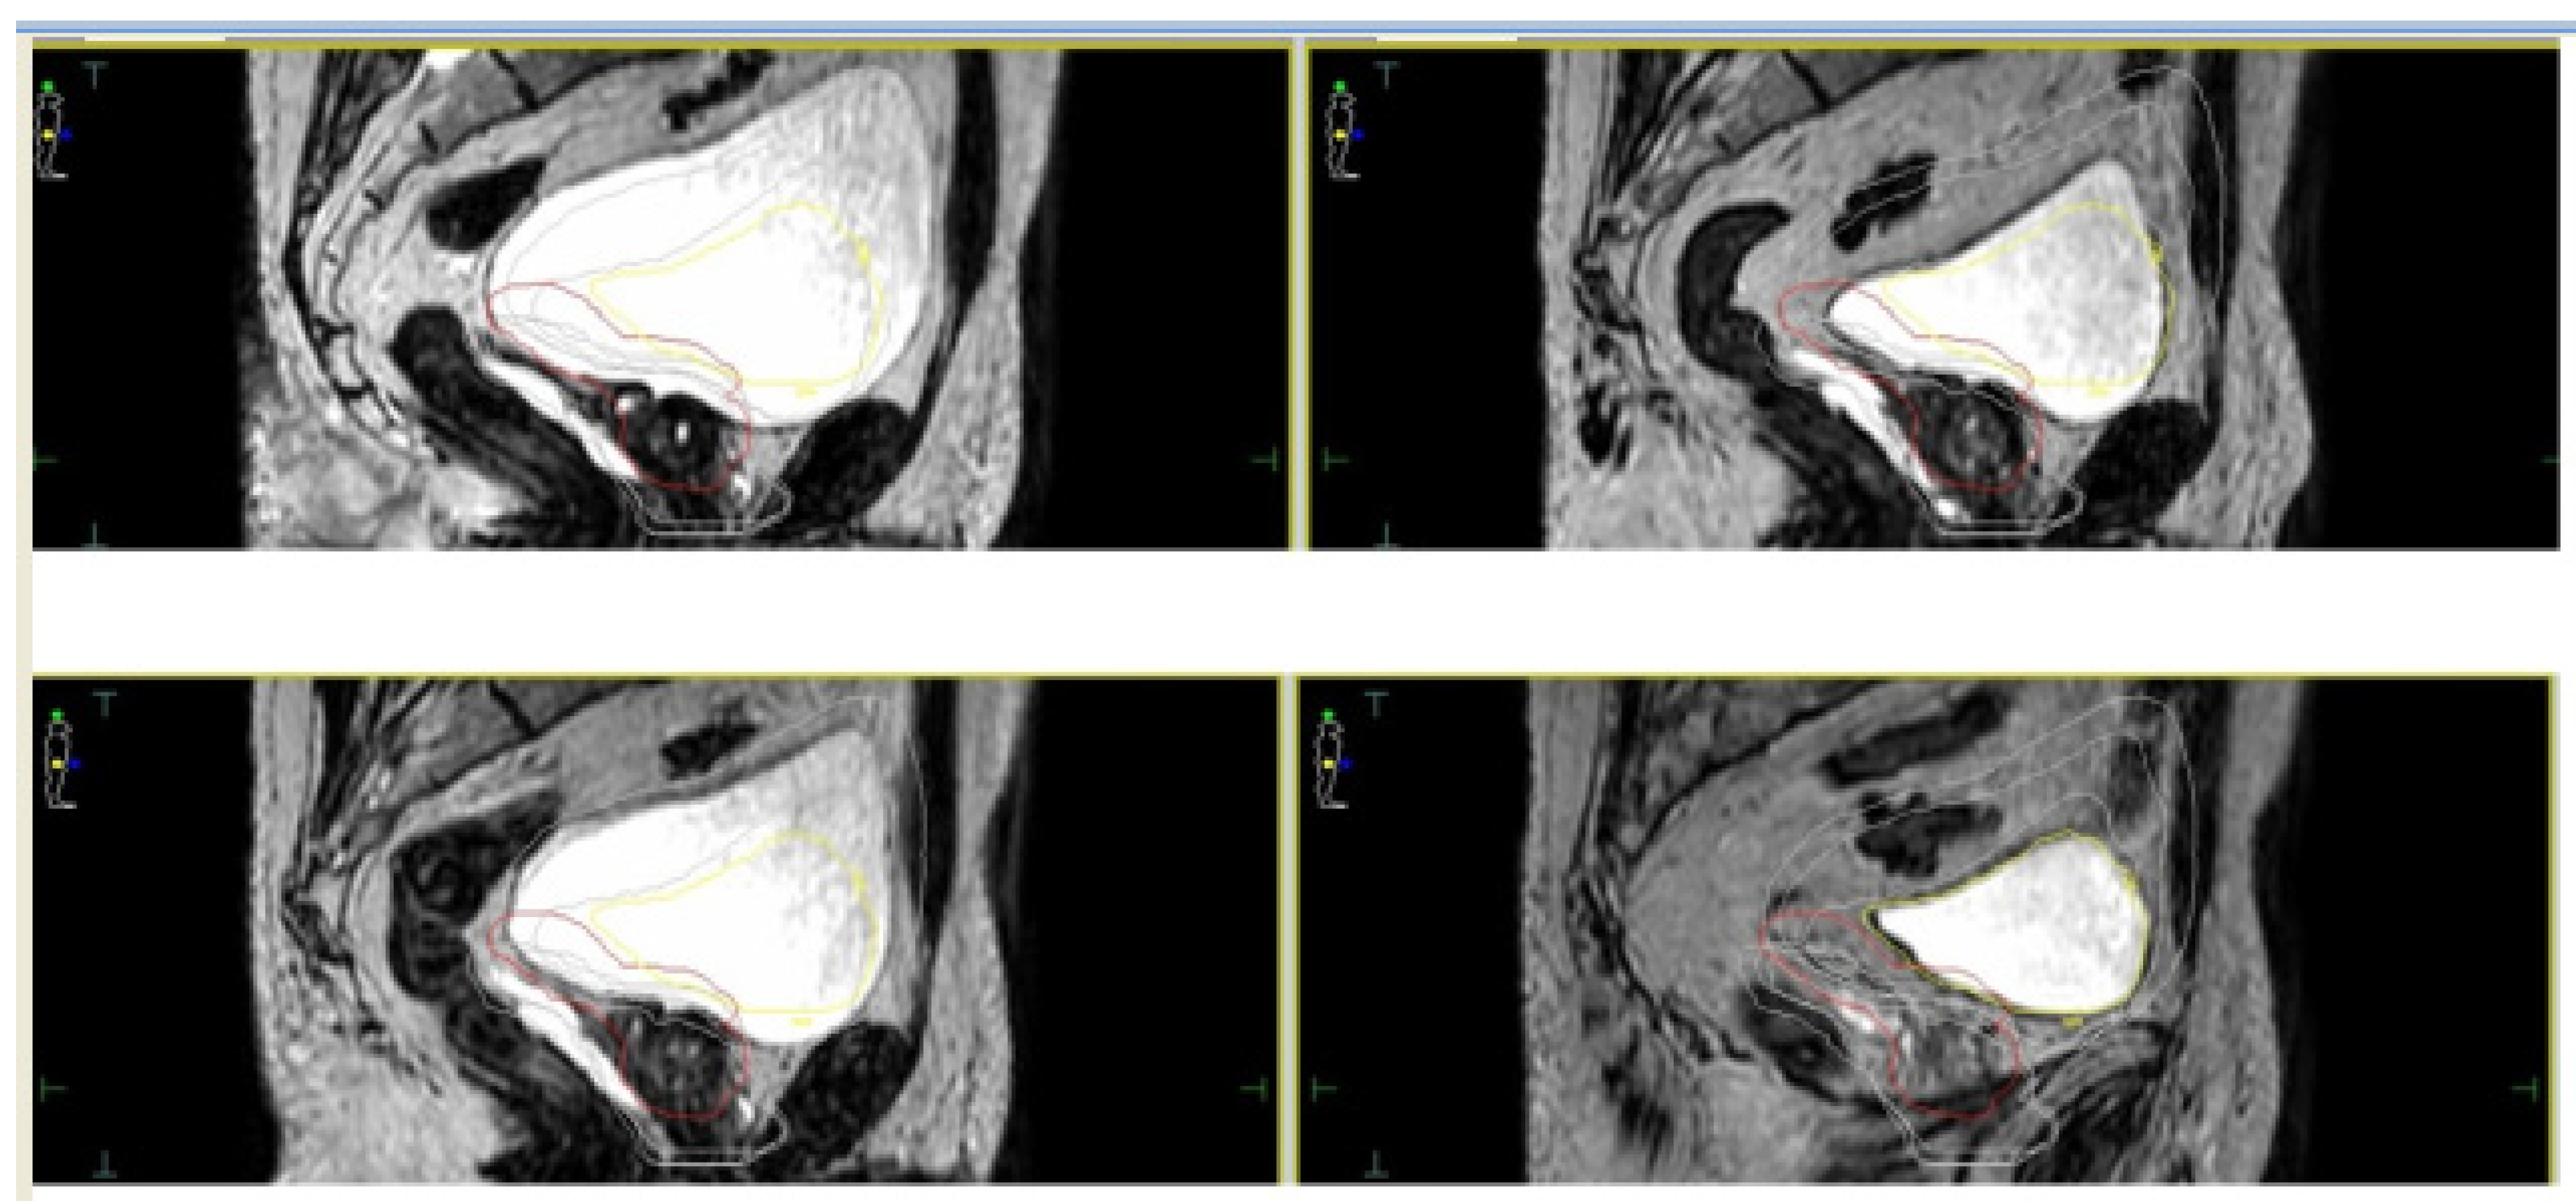

- Alongi, F.; Rigo, M.; Figlia, V.; Cuccia, F.; Giaj-Levra, N.; Nicosia, L.; Ricchetti, F.; Vitale, C.; Sicignano, G.; De Simone, A.; et al. Rectal spacer hydrogel in 1.5T MR-guided and daily adapted SBRT for prostate cancer: Dosimetric analysis and preliminary patient-reported outcomes. Br. J. Radiol. 2021, 94, 20200848. [Google Scholar] [CrossRef] [PubMed]

- Cuccia, F.; Mazzola, R.; Nicosia, L.; Figlia, V.; Giaj-Levra, N.; Ricchetti, F.; Rigo, M.; Vitale, C.; Mantoan, B.; De Simone, A.; et al. Impact of hydrogel peri-rectal spacer insertion on prostate gland intra-fraction motion during 1.5 T MR-guided stereotactic body radiotherapy. Radiat. Oncol. 2020, 15, 1–9. [Google Scholar] [CrossRef] [PubMed]